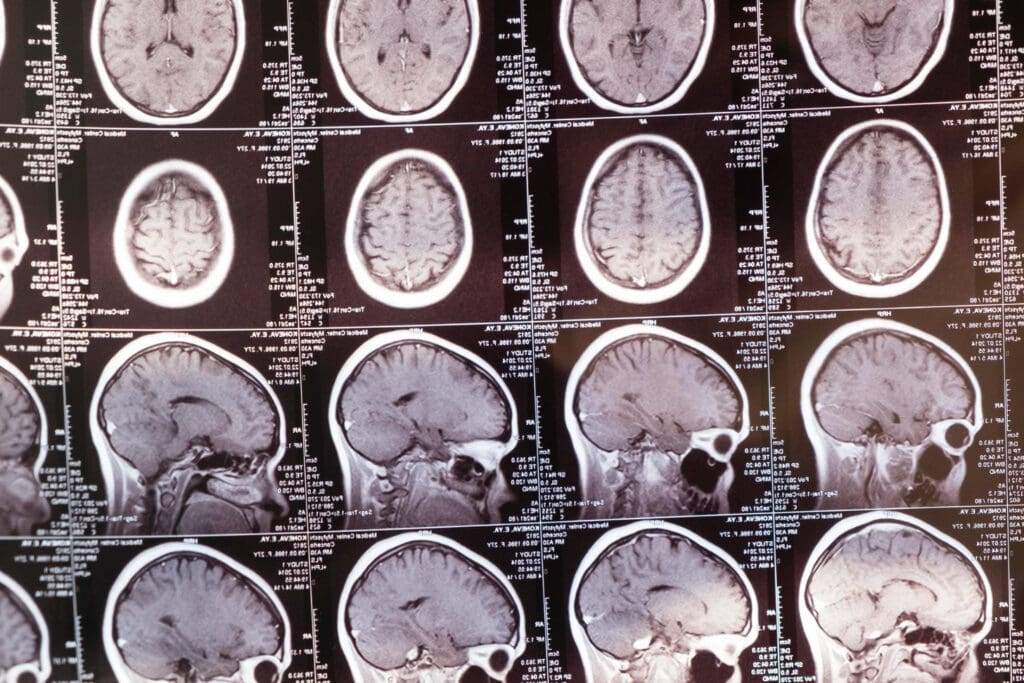

Receiving a brain cancer diagnosis can be overwhelming, and the question of whether it’s curable is a pressing concern for many patients and their families. At Liv Hospital, we understand the complexity of this question and are committed to providing the latest advancements in brain cancer treatment.

While a definitive cure for brain cancer remains elusive, significant progress has been made in treating various types of brain tumors. Our team is dedicated to delivering personalized care, with treatment plans tailored to each patient’s unique needs.

We explore the potential for curing brain tumors, with a focus on the latest research and survival statistics. Our commitment is to provide world-class cancer care, offering renewed hope to patients and their families.